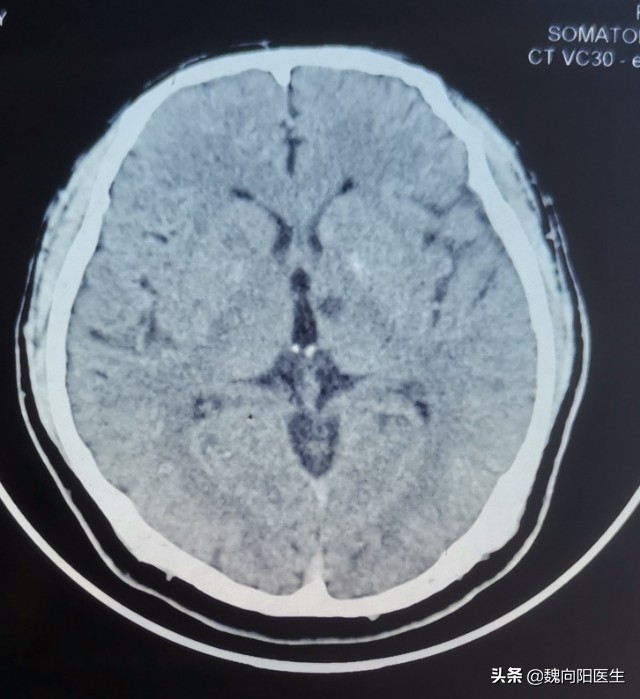

很多人在正常体检的时候查头CT或者头核磁,报告会诊断:腔隙性脑梗死。

腔隙性梗塞是由于深部小穿支动脉等血管发生了病变。由于只是发生在脑白质深部小血管中,因此被称为脑小血管病。

腔隙灶直径一般在5-15mm之间,大于10mm者有时称为巨腔隙灶。